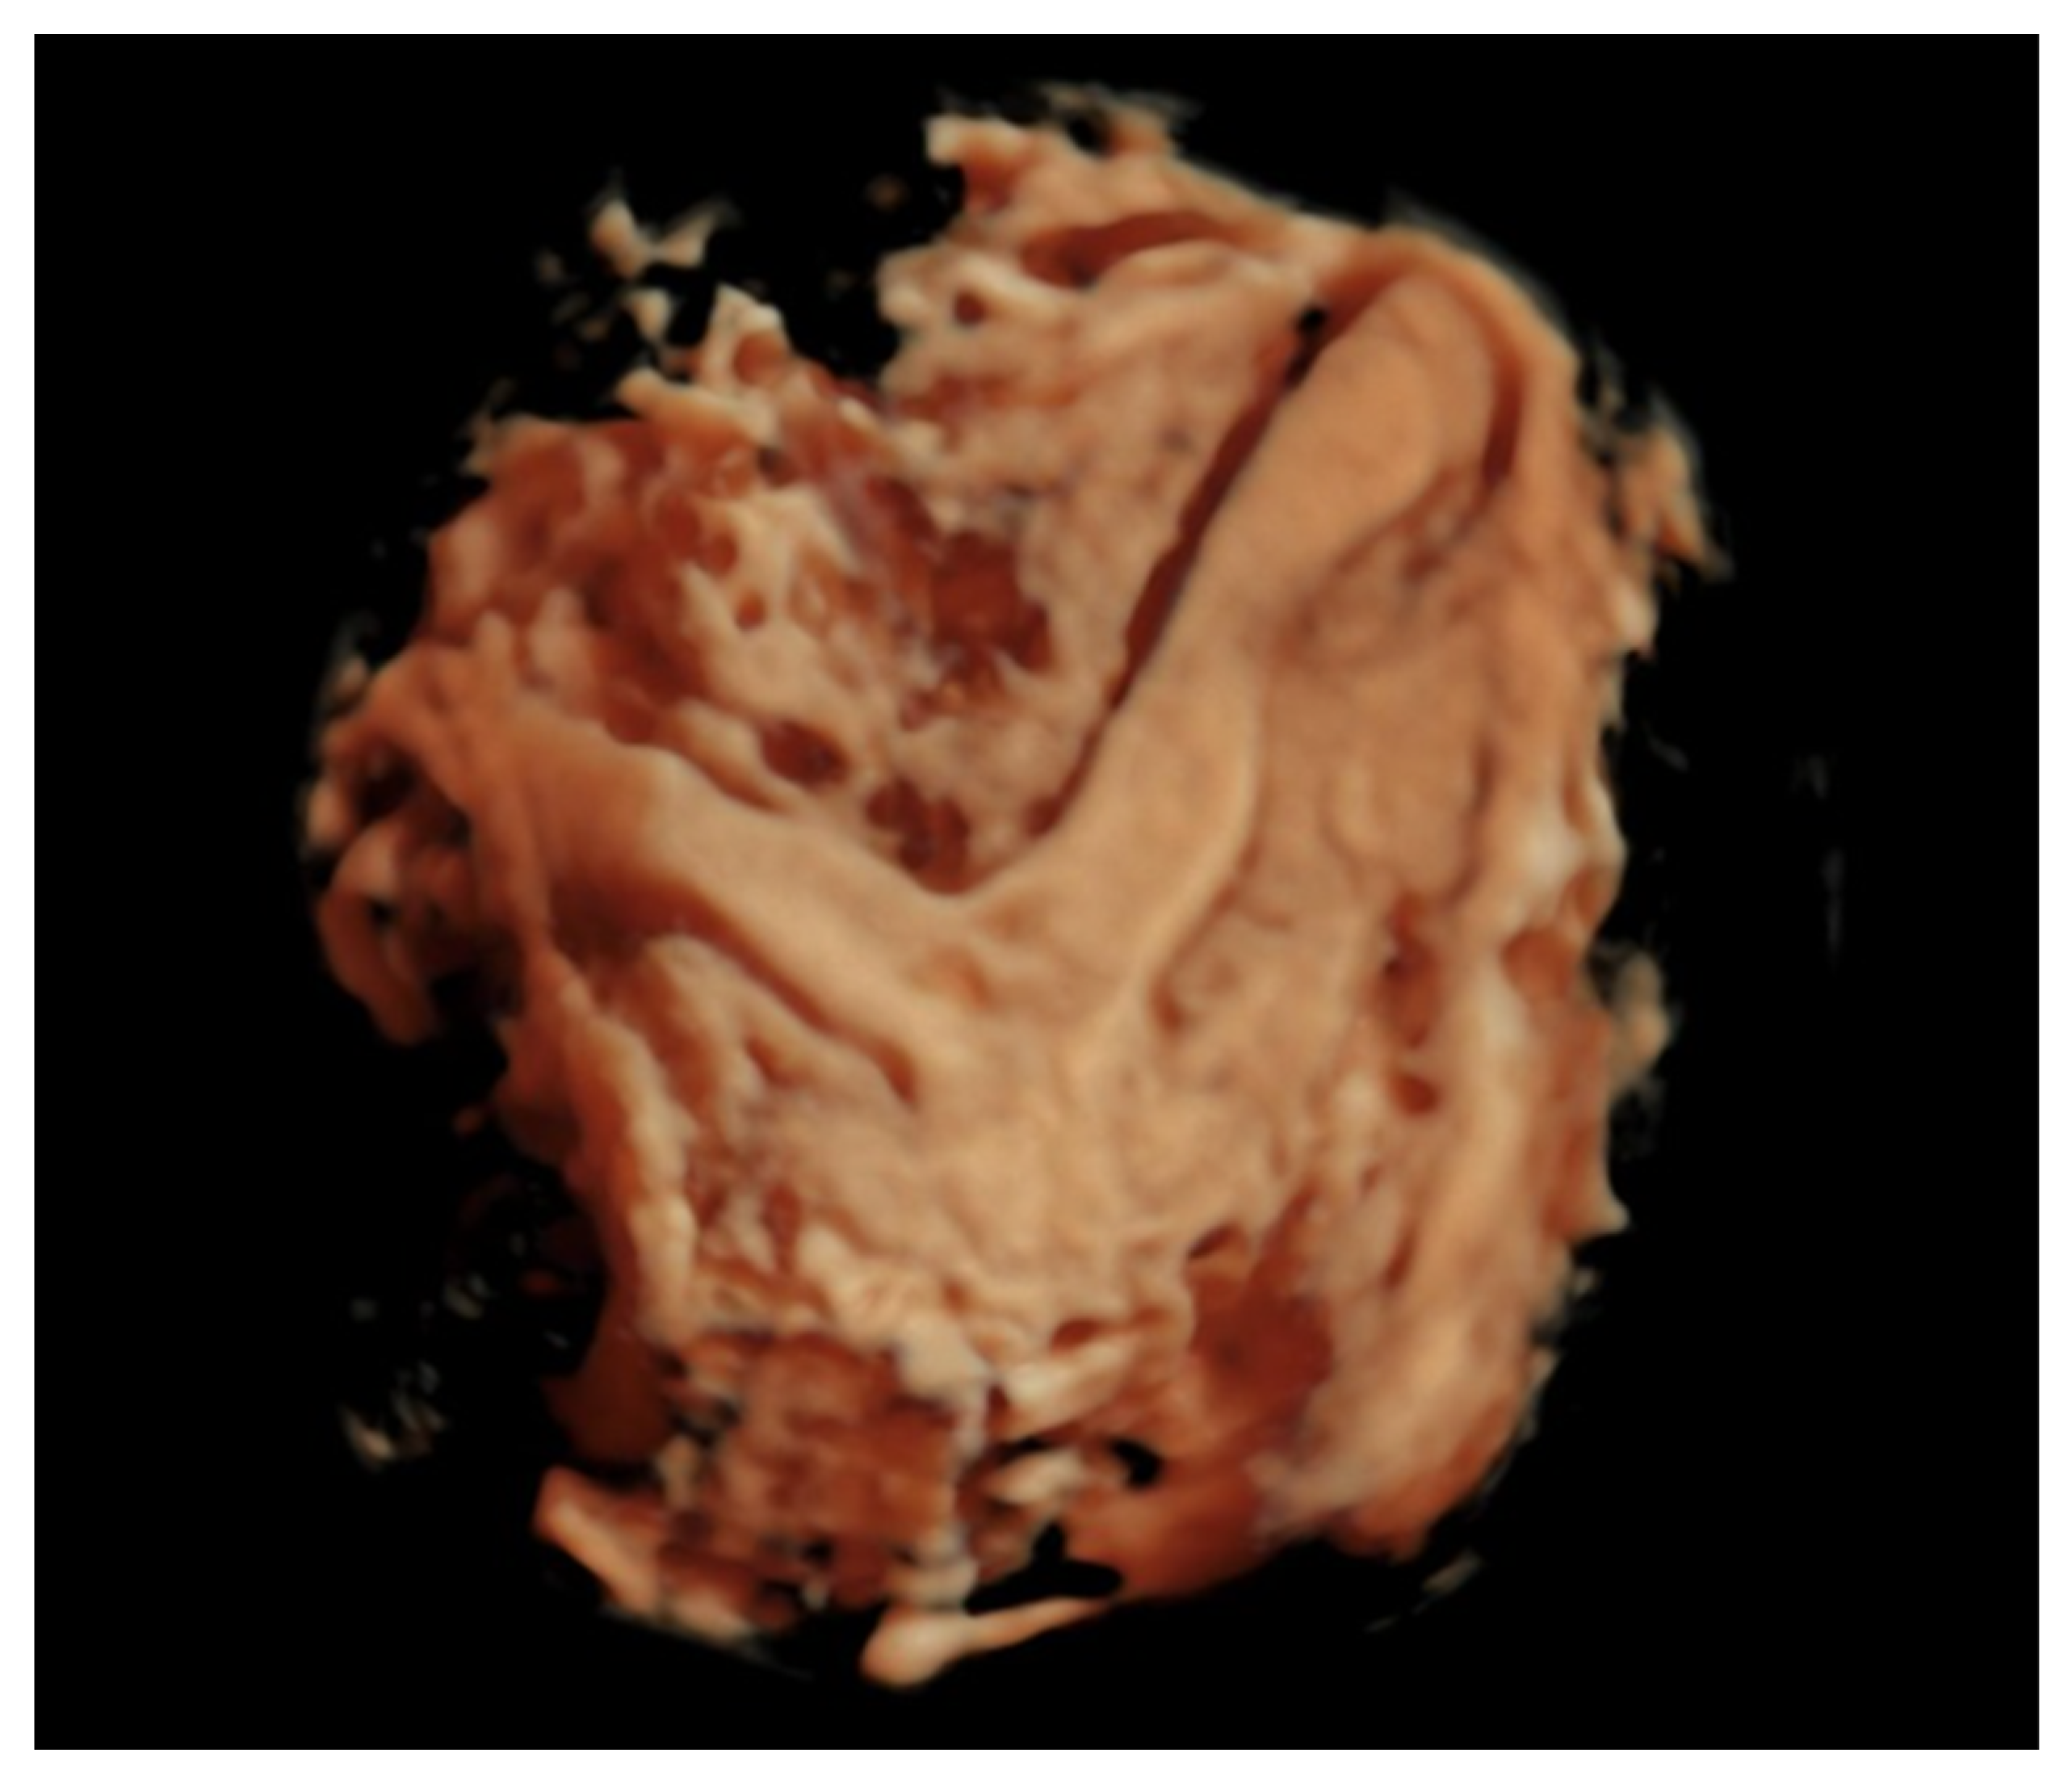

3.2. Patient Number 2

| Gestational Age (Weeks) | 27 Weeks | 29 Weeks | 32 Weeks 2 Days | 32 Weeks 4 Days |

|---|---|---|---|---|

| EGF | 967 | 1186 | 1548 | 1560 |

| Hadlock % | 15 | 12 | 4.1 | 3.1 |

| BPD | 5.96 | 6.43 | 6.76 | 7.08 |

| HC | 25.49 | 26.8 | 28.7 | 29.35 |

| AC | 22.2 | 23.83 | 25.94 | 25.95 |

| FL | 4.99 | 5.37 | 5.97 | 5.87 |

| AFI modified | no | no | no | no |

| Barcelona index | no | no | Barcelona stage I | Barcelona stage I |

| IVS thickness (mm) | 1.91 | 2.14 | 4.03 | 4 |